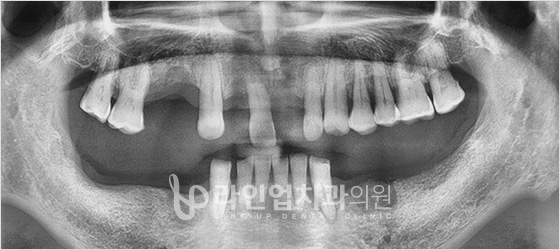

Before

After

Дээд арааны имплант